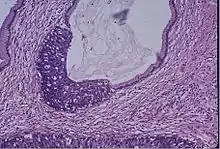

Cervical screening by the Pap test or other methods is highly effective at detecting and preventing cervical cancer, although there is a serious risk of overtreatment in young women up to the age of 20 or beyond, who are prone to have many abnormal cells which clear up naturally.[26] There is a considerable range in the recommended age at which to begin screening around the world. According to the 2010 European guidelines for cervical cancer screening, the age at which to commence screening ranges between 20 and 30 years of age, "but preferentially not before age 25 or 30 years", depending on the burden of the disease in the population and the available resources.[27]